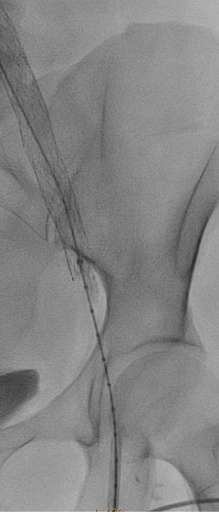

בתמונה 2:

- ורידים מורחבים "גודש ורידי אגן"